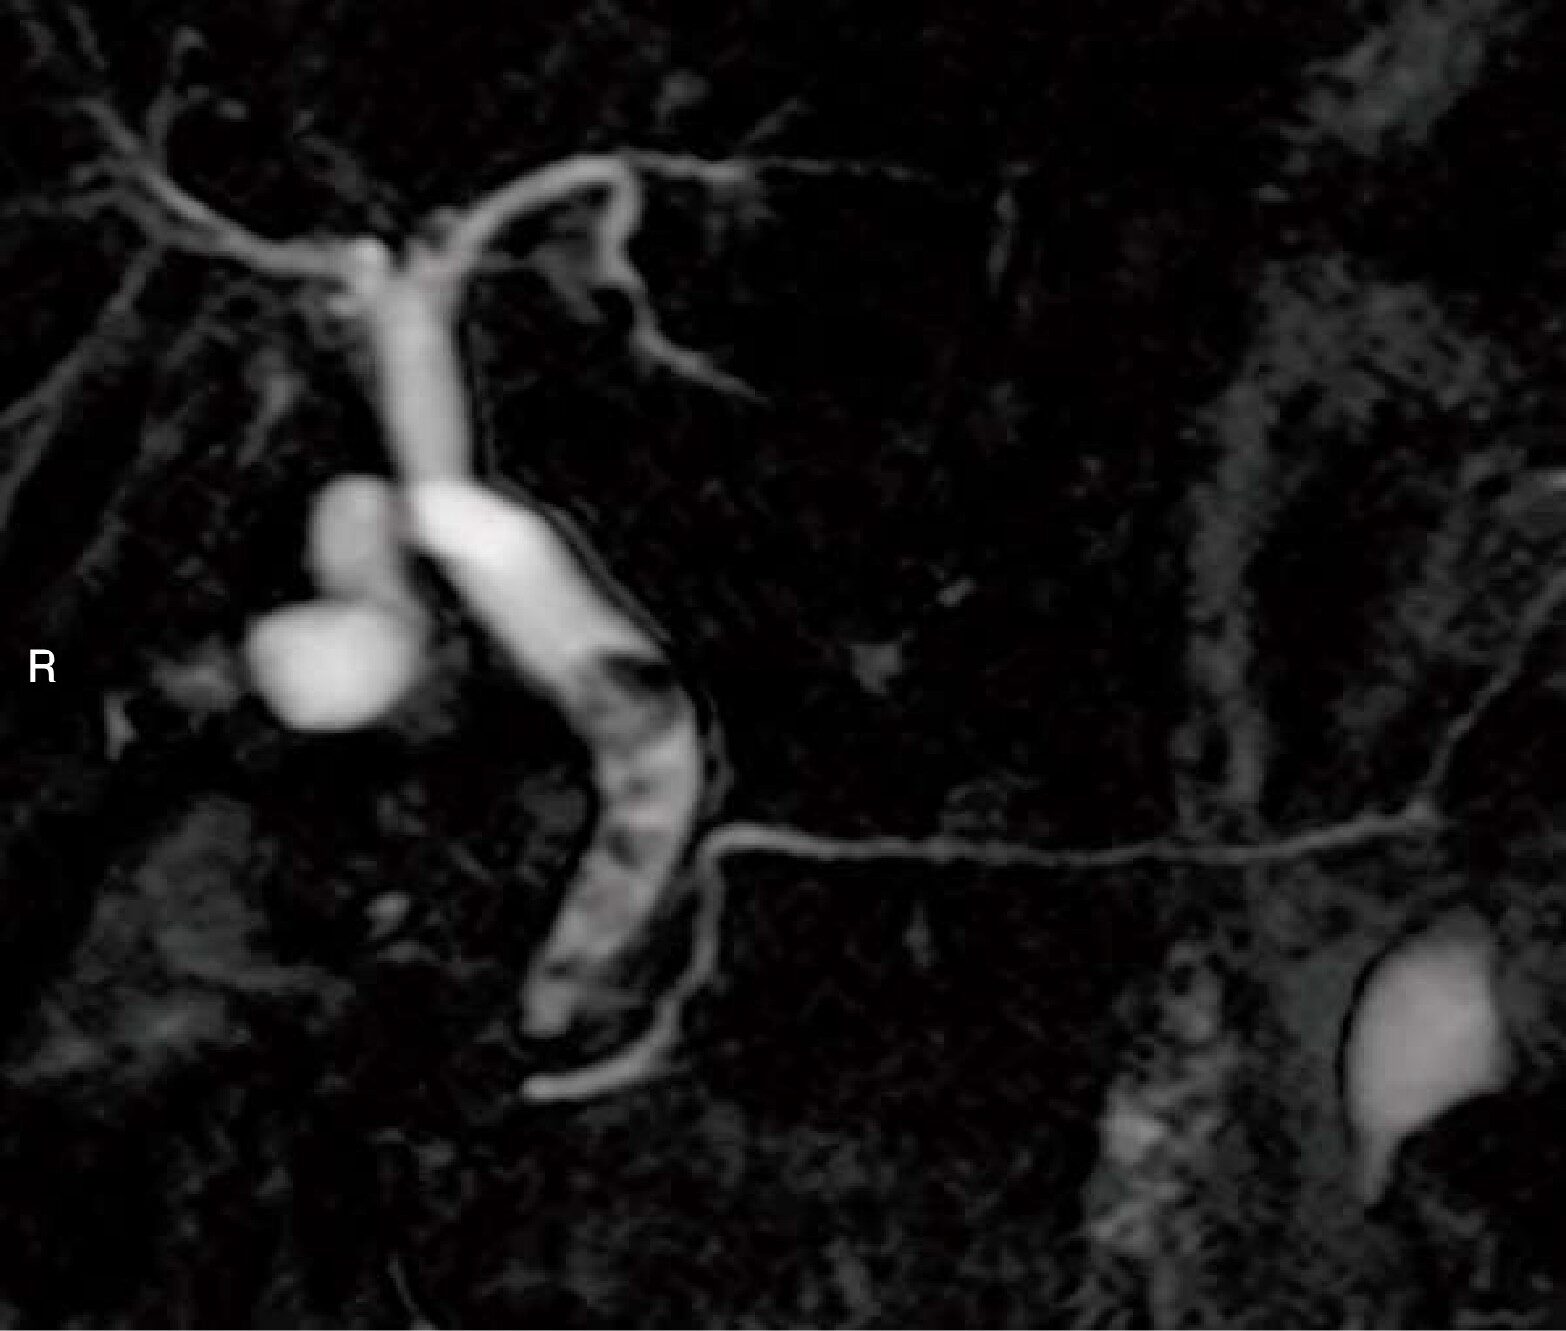

MRCP像(別冊No.5)を別に示す。結石が存在するのはどれか。